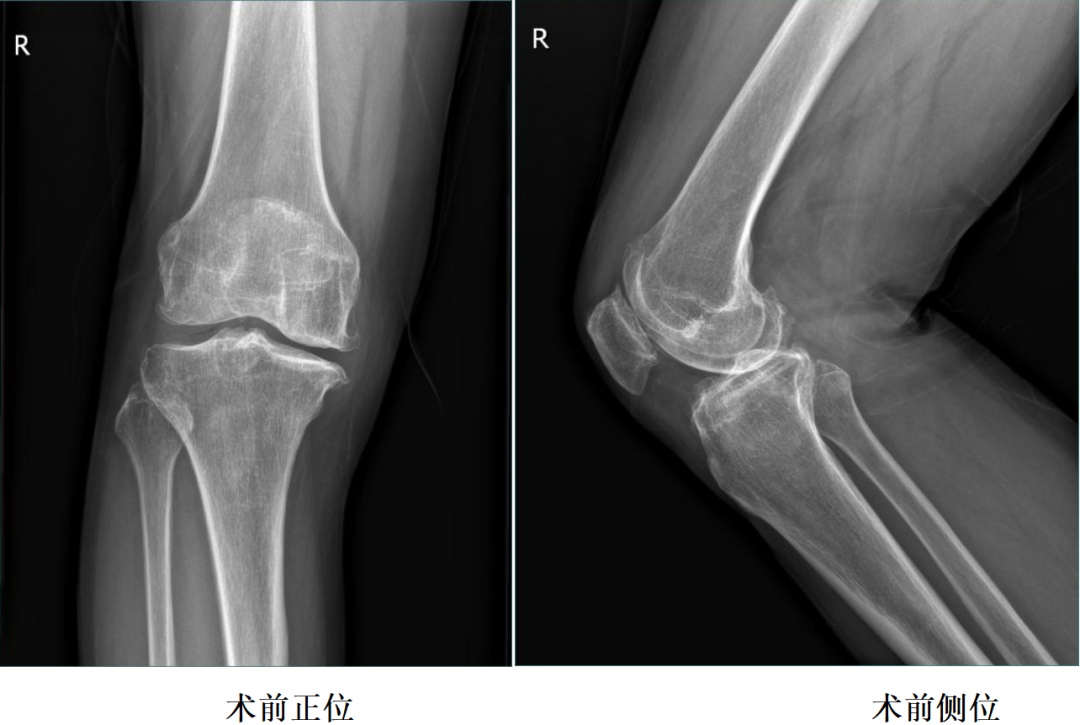

二、术前X片

X-Ray:右膝内侧间隙明显狭窄,站立位内侧间隙消失,外侧间隙正常,膝关节稳定。

诊断:右膝关节内侧间室OA。